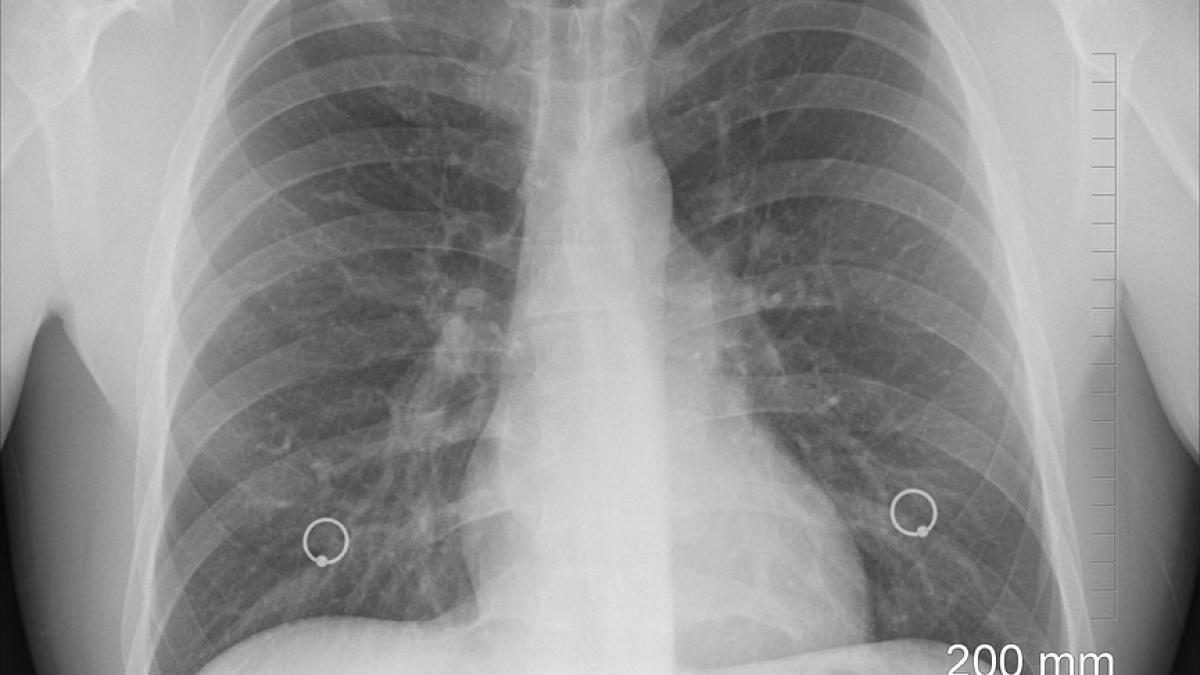

plamani-imbatranire-30-de-ani_86220400 Nu doar pielea îmbătrânește, ci și plămânii. Dr. Bilic: Începe la vârsta de 30 ani. Există 2 soluții / Foto: Pixabay

După vârsta de 30 de ani, plămânii îmbătrânesc accelerat, avertizează Mihaela Bilic, Medicul nutriționist a explicat în cadrul emisiunii Doctor de Bine de la Pro Tv ce putem face pentru a încetini acest proces.

"Nu doar pielea îmbătrânește, ci și plămânii. Vinovatul este oxigenul fără de care nu putem trăi și care ne ruginește în mod inevitabil. Îmbătrânirea pulmonară începe la vârsta de 30 ani. Studiile au arătat că insuficiența respiratorie acută poate apărea rapid, în 24 ore, dacă suntem expuși la o atmosferă compusă exclusiv din oxigen.

Această toxicitate se explică prin producția de radicalii liberi în concentrații mari, care depășesc capacitatea antioxidantă a organismului. Aerul pe care-l respirăm în mod obișnuit produce leziuni minime, dar se pot acumula în timp, odată cu înaintarea în vârstă.